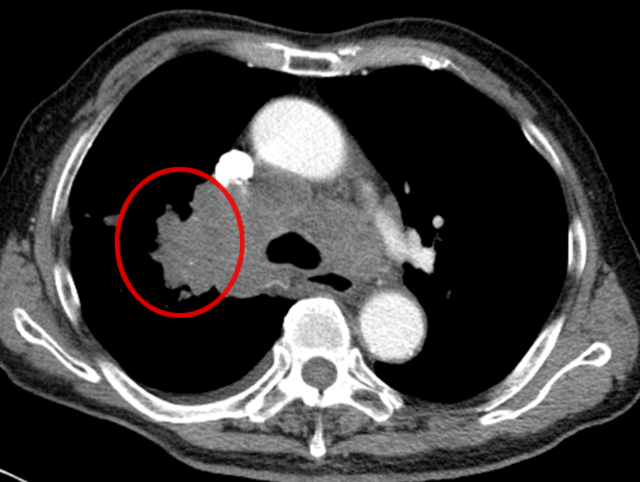

操作很快完成,术中术后都没有出现血气胸,老先生精神状态良好,也没觉得胸闷胸痛。3 天后病理报告出来了:小细胞癌!原来这不是结肠癌肺转移,而是老爷爷患上了第二种原发肿瘤,是肺里地地道道的 “原住民”。

还有另一位患者,肺部结节只有 15mm,还合并了空洞,医生同样通过 CT 引导精准定位,成功完成经皮肺穿刺取到病理组织,最终诊断为 “腺癌”(免疫组化提示 CK7、TIF-1、NapsinA 阳性,排除其他类型肿瘤)。

它就像一位精准定位的 “远程射手”:在 CT 的 “透视眼” 帮助下,医生能清晰看到肺部病变的位置、大小,以及周围的血管、气管等结构;随后用一根细针,从胸壁皮肤轻轻穿刺进入肺部,直达病变部位,抽取少量组织送检。

这种方式尤其适合深部或微小病灶—— 比如位置藏得深、体积小到 1cm 左右的病灶,CT 引导几乎是实现精准穿刺的唯一选择,能帮医生在不 “大动干戈” 的情况下明确肿瘤身份。